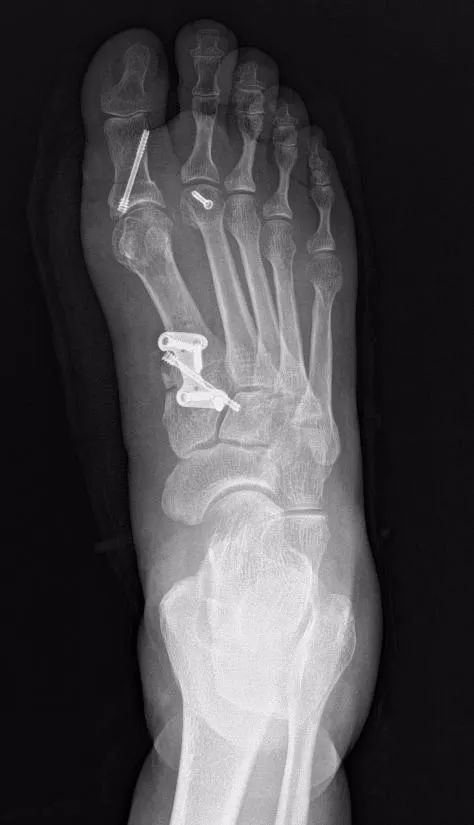

常规的手术方法都是从二维平面上来纠正踇外翻,但事实上踇外翻是一种三维的畸形,常规的术式无法将第一跖骨解剖复位。为了矫正王阿姨的畸形,让王阿姨能够正常的穿鞋和走路,经过仔细的术前准备,杨云峰主任选择了右足第一跖骨截骨+去旋转复位,从三维上将第一跖骨及籽骨恢复到正常解剖位置,第二跖骨采用切开复位+跖板修复手术,将第二足趾完全复位至正常位置,帮助患者解决了穿鞋难、走路痛的问题。

踇外翻畸形是一种常见的足畸形,是指第一跖骨内翻内旋以及趾骨外翻,可合并其它足趾的偏斜、骑跨。除了穿鞋不当以外,肥胖、遗传、年龄、类风湿性关节炎、韧带松弛等原因都可能引起踇外翻畸形的发生。踇外翻是一种复杂的解剖畸形,严重的踇外翻畸形可出现足底的疼痛及感觉减退,此时及早手术才是矫正踇外翻畸形的最佳解决办法。